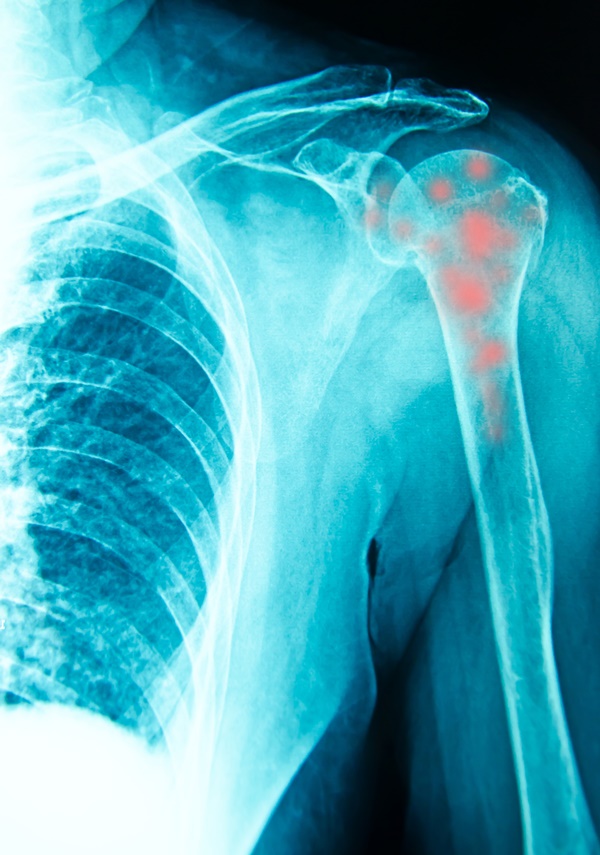

흡연, 혈액순환 저하, 당뇨병처럼 혈관 건강에 영향을 주는 전신 질환이 있으면 힘줄로 가는 산소와 영양 공급이 떨어져 석회화 건염 원인 더 잘 쌓일 수 있습니다. 건강검진 엑스레이에서 우연히 석회가 발견되는데 통증이 없는 분들도 있는데요, 석회 자체보다 석회가 녹아 없어지려는 과정에서 염증이 생길 때 통증이 폭발하는 경우가 많다는 점이 특징입니다.

실제 진단에서는 엑스레이와 초음파로 석회 위치와 크기를 확인하고, 필요하면 자기공명검사 같은 정밀 검사를 통해 힘줄 파열 여부나 주변 구조의 상태를 함께 평가합니다. 어느 부위든 석회화 건염이라는 이름 안에 들어가지만, 생활에서 불편하게 느껴지는 동작과 재활 방향은 조금씩 달라질 수 있습니다.